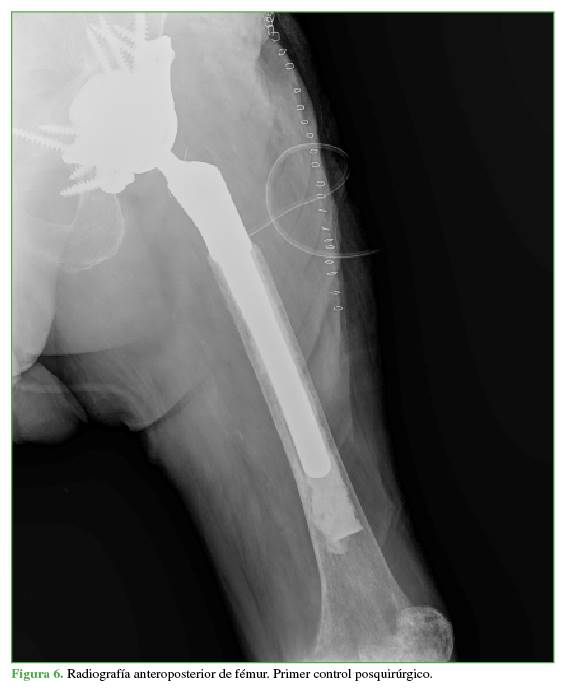

Tras un exhaustivo y sistematizado lavado pulsátil con suero fisiológico, se procedió con una osteotomía femoral proximal de 7 cm, se fresó el canal y se colocó un vástago femoral tumoral cementado de 18 x 150 mm. Antes de finalizar la cirugía, se comprobó la estabilidad mecánica del material protésico que resultó óptima, y se completó la cirugía mediante un reanclaje de la musculatura glútea y abductora a una malla de tereftalato de polietileno. Dicho componente es un elemento mecánico restrictivo que, posteriormente, genera una neocápsula junto a los elementos anclados y aporta estabilidad articular (Figura 6).

El paciente no requirió transfusión de concentrados de hematíes durante la hospitalización. Antes del alta, consiguió deambular 20 pasos seguidos con la ayuda de un andador, con una independencia relativa.